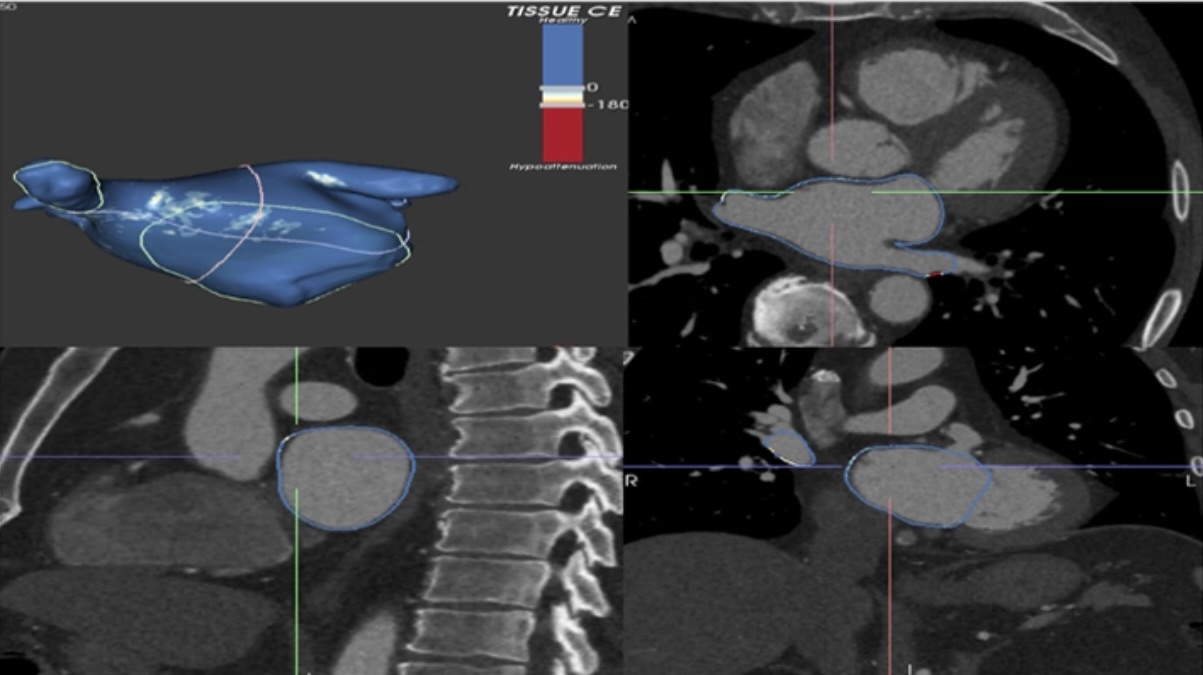

Objective: The purpose of this study was to quantitate the extent of LA LM using contrast enhanced computed tomography (CECT) and to examine its association with intracardiac electrogram characteristics using high density electroanatomic mapping in patients referred for AF ablation.

Methods: The retrospective cohort included consecutive patients who underwent CECT and LA high-density mapping (Pentaray, Biosense Webster) prior to AF ablation between January 2021- 2023. Univariable associations were examined using nonparametric tests. The association of bipolar voltage amplitude and mid-LA myocardial CECT image intensity (< 0 Hounsfield units indicative of LM, ADAS 3D software), at each electroanatomic map point, was examined using a mixed effects linear regression model clustered by patient.

Results: The cohort consisted of 34 patients with mean age 66.4 ± 9.5 years, BMI of 31.7 ± 9.5 kg/m2, left atrial volume index (LAVI) 38.0 ± 8.1 mL, and EF 51 ±13%. Of all patients, 41% were female, 65% had persistent AF, 74% had hypertension, 41% had coronary disease, 12% had diabetes, 33% had sleep apnea, and 15% had prior stroke or TIA. LM was detected among 53% of patients (95% CI 36-69%), and was unassociated with age, BMI, LAVI, AF type, sex, diabetes, sleep apnea, or hypertension. Bipolar voltage was associated with CECT attenuation (-0.2 mV/ Hounsfield unit, P<0.001), but was unassociated with LM.